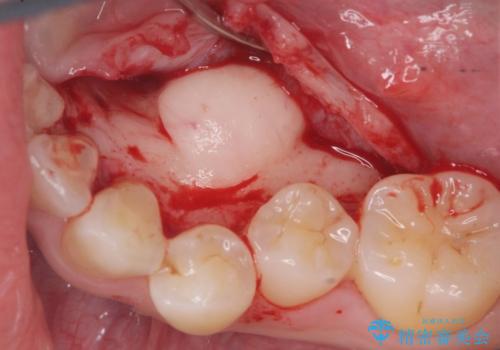

上下の歯のがたつきを改善するマウスピース矯正治療と、下顎に見られる大きな骨隆起を外科的に除去する治療計画を進めていきます。

骨隆起の除去は、静脈内鎮静法を用いてほとんど記憶のないうちに行うことができます。

歯並びが改善したとともに、骨隆起を除去したことで舌をしまうスペースも増え安定した口腔内環境を確立することができました。

- 外科手術のため、術後に出血、痛みや腫れ、違和感を伴います